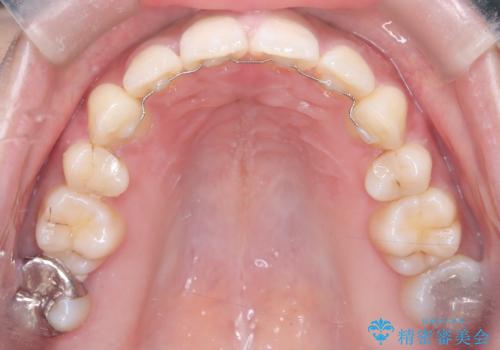

- 矯正装置

- 審美ワイヤー

今回の矯正治療では、口元の突出感を解消するためのスペースを確保するため、計画通り上下左右4本の小臼歯を抜歯しました。装置には、確実な歯の移動と細やかな調整が可能なワイヤー矯正を採用。抜歯によってできたスペースを最大限に利用し、前歯を奥へ、そして垂直的に慎重に移動させました。

治療の結果、長年のコンプレックスであった口元の突出感が大幅に解消され、横顔のライン(Eライン)が美しく改善しました。機能的な咬み合わせを確立すると同時に、患者様が望んでいた審美的な口元を獲得していただけました。